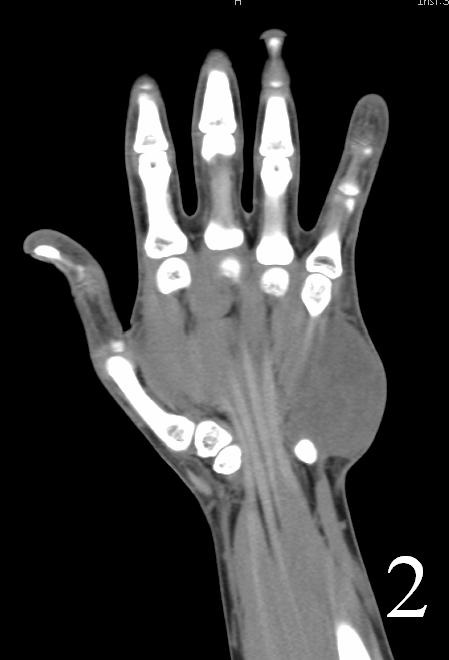

CT

- Shows a heterogeneous mass sometimes involving adjacent bone

- After contrast, the mass enhances (Fig. 2, Fig. 3)

- Hard to identify necrosis, hemorrhagic or calcification.

Fig. 2-3: Coronal and axial (Fig. 3) CT of a rhabdomyosarcoma of the hand shows a well circumscribed mass isointense to muscle